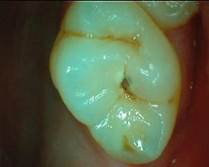

Although the literature agrees that early-stage (non-cavitated) carious lesions classified as ICDAS 1 and 2 can be treated with sealants, there are fewer studies supporting their use in lesions with localized enamel breakage, ICDAS 3 (microcavitated), for arresting progression (photo 3). A randomized controlled trial published in 2019 concluded that sealing ICDAS 3 carious lesions in permanent molars appears to effectively halt their progression. Moreover, this approach preserves tooth structure, reduces chair time, alleviates fear, cuts costs, and broadens access to dental care 3.